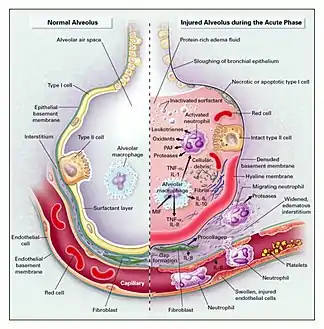

The epithelial lining of alveoli are composed of two different types of cells. Alveolar type I epithelial cells comprise about 80% of the alveolar surface area and are primarily responsible for gas exchange.[5] Alveolar type II epithelial cells play the critical roles of producing surfactant, moving water out of the airspaces, and regenerating alveolar epithelium.[5] The alveolar type II epithelial cells are more resistant to damage, so after an insult to the alveoli, most of the damage will occur to the alveolar type I epithelial cells.[5]

Once the initial insult has damaged the alveoli and begun the process of DAD, the condition will typically progress in three phases: exudative, proliferative, and fibrotic.[6] Below are the description of the phases, paraphrased from Sweeney et al. (2016).[6]

- Exudative Phase (1–7 days): After the initial insult to the alveoli, immune cells (neutrophils and macrophages) are recruited to the alveoli, which can cause more damage through their nonspecific defensive mechanisms. Since the epithelial lining is damaged it allows plasma and proteins to leak in to the airspace, accumulating fluid (otherwise known as edema). Additionally, since the epithelial lining is damaged there is limited ability to pump this edema out of the airspace and back in to the interstitium. The presence of this edema has the following detrimental impacts:

- The edema contributes to the deposition of a hyaline membrane (composed of dead cells, surfactant, and proteins) along the alveolar walls. Hyaline membranes are characteristic of DAD.

- The edema interferes with the naturally occurring surfactant, which is critical for reducing surface tension and allowing alveoli to remain open and allow air in for gas exchange.

- Proliferative/Organizing Phase (1–3 weeks): This phase is characterized by recovery. The epithelial lining is repopulated with alveolar type II epithelial cells which will eventually differentiate into alveolar type I epithelial cells. While the type II epithelial cells are repopulating the epithelial surface they are also performing the critical task of transporting the edema out of the airspace and back into the interstitium. Meanwhile, in the airspace, macrophages are clearing cellular debris.

- Fibrotic Phase (after 3 weeks, if occurs): not all courses of DAD result in a fibrotic phase. This phase occurs if the alveolar collagen that is deposited during the acute exudative phase fails to be resorbed, resulting in limitations of alveolar expanse and subsequently gas exchange.